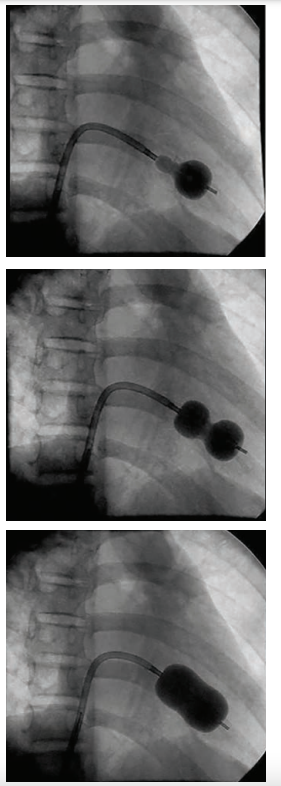

The typical step-wise Inoue balloon (Toray) technique for PBMV involves assessing a maximal balloon size using the patient’s height; inflations usually begin with a balloon size several millimeters smaller (Figure 6).

After each inflation, hemodynamics are reviewed for reduction of gradient and induction of any new mitral regurgitation. This is done by a combination of echocardiography (transesophageal or intracardiac echo, and occasionally, by transthoracic echo) and hemodynamics. A decrease in gradient of at least 50% and particularly an increase in mitral insufficiency by one grade should signal the operators to stop. Figure 7 shows this stepwise dilatation technique with an unfortunate result. The initial tracing (Figure 7, left panel) is consistent with severe mitral stenosis in a severely symptomatic woman. After initial inflation the gradient is significantly reduced (Figure 7, middle panel), but the operators continued to attempt to achieve a lower residual gradient. The next inflation with a 1 mm-larger balloon resulted in abolition of the gradient, but produced a giant ‘v’ wave to 70 mmHg (Figure 7, right panel), consistent with severe iatrogenic mitral insufficiency. At surgery to repair the torn valve, a commissure split was the predominant mechanism. The patient did well after emergency mitral valve replacement.